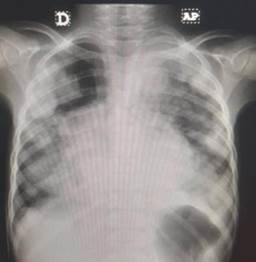

Se realiza estudio radiológico de tórax, apreciándose lesiones radiopacas, redondeadas, múltiples en región mediastínica y periférica del tórax. Es evaluada por el servicio de Neumonología considerándose patología neoplásica pulmonar, por lo que se solicita ecografía y Tomografía Axial Computarizada (TAC) de tórax.

La ecografía torácica (Imagen 4) muestra lesiones de aspecto gelatinoso de bordes irregulares en pleura visceral y parietal de aspecto mamelonado, compatible con infiltración pleural y discreto derrame pleural de aproximadamente 20 ml. Estudio del líquido pleural: Citoquímico normal, inmunohistoquímica negativa, citomorfológico negativo para células malignas.